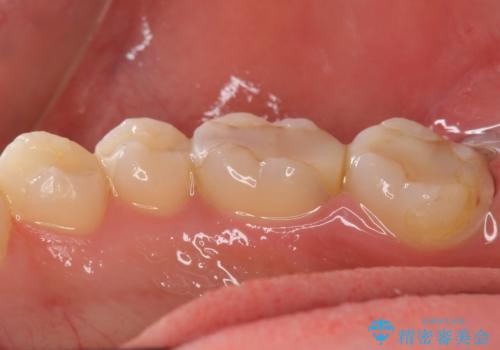

精査したところ、ほとんどの歯が保険内のレジンで充填されており、咬み合わせも悪く咬合していない歯もありました。

虫歯をしっかりと治療したのち、オールセラミッククラウンによる補綴治療を行いました。

不適なレジン充填によるデコボコがなくなったことで歯磨きしやすくなり、また気にされていた咬み合わせも良くなり、ご満足頂けました。

クラウンの種類:オールセラミッククラウン スタンダード

シェード:NW0